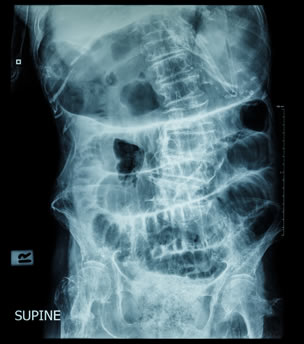

Οι απλές ακτινογραφίες κοιλίας αποτελούν την πιο σημαντική διαγνωστική δοκιμασία στον ειλεό. Πρέπει να γίνονται σε όρθια και σε ύπτια θέση. Αναδεικνύονται διατεταμένες έλικες λεπτού εντέρου (ημισεληνοειδείς διαυγάσεις) σε διάταξη κλίμακας στην ύπτια ακτινογραφία και υδραερικά επίπεδα, τα οποία είναι εμφανή στην απεικόνιση σε όρθια θέση.

Ακτινογραφία σε όρθια θέση

Αυτά τα ευρήματα μπορεί να είναι ελάχιστα ή και απόντα στην πρώϊμη φάση της απόφραξης, στην εγγύς απόφραξη, την απόφραξη «κλειστής έλικας», ιδιαίτερα σε ισχαιμική περίσφιξη της τελευταίας, και σε περιπτώσεις που οι έλικες είναι γεμάτες με πολύ εντερικό υγρό και περιέχουν λίγο αέρα. Σε απόφραξη πέραν του 24ωρου, ο αέρας και τα κόπρανα έχουν κενωθεί από το παχύ έντερο, και αυτό φαίνεται στην απλή ακτινογραφία. Στην πρώϊμη φάση ωστόσο, αλλά και στις περιπτώσεις που η απόφραξη είναι μερική και ο ειλεός ατελής, κάποια ποσότητα αέρα ανευρίσκεται στο παχύ έντερο, και αυτό αποτελεί ένα από τα στοιχεία που διαχωρίζουν τον πλήρη από τον ατελή ειλεό.